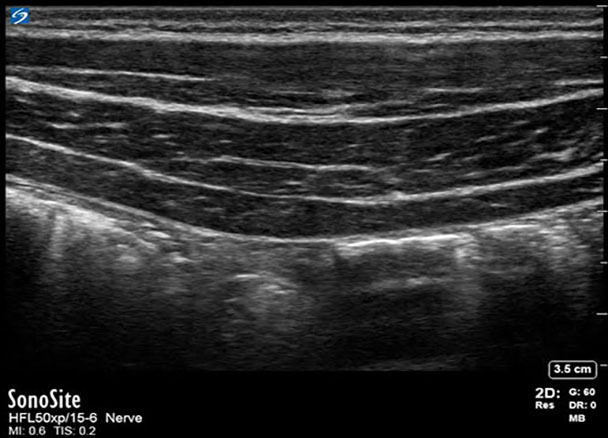

X-Porte : Image du nerf du plan du muscle transverse de l'abdomen